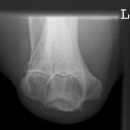

Ellenbogen seitlich (2. Ebene radio-ulnar)

Qualitätskriterien

Ellenbogengelenk vollständig seitlich orthograd abgebildet. Humeroulnar Gelenkspalt einsehbar. Humeruskondylen müssen sich decken, das Radiusköpfchen soll gut beurteilbar sein.